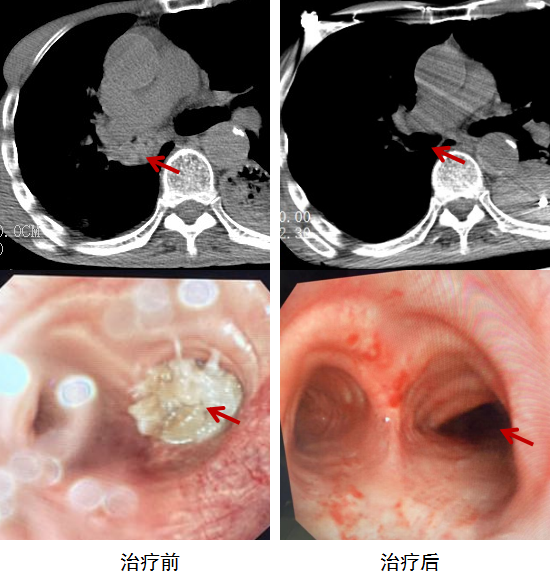

結合老伯之前進食蹄髈,且有食道癌手術史,吞嚥功能較弱,石峻醫生評估生命體徵後,立即安排做了胸部CT以明確異物阻塞部位情況。檢查顯示,右主支氣管高密度影填充。於是,急診室緊急請呼吸科會診,大家考慮氣道異物梗阻可能性大,需進行支氣管鏡下異物清除術。

呼吸與危重症學科王維斯醫生介紹,手術中,他們發現老伯的右主支氣管裡有白色固態異物,管腔被完全堵住,氣管鏡無法進入,只好透過左主支氣管及其分支,使用活檢鉗、圈套、冷凍探頭將異物取出,老伯的氧飽和度隨即上升至100%。

“豬蹄的筋皮很軟滑,用活檢鉗無法鉗住,我們先用圈套器做切割分解大塊異物,部分質地較硬的透過圈套器取出,剩餘綿軟易碎的透過冷凍粘附後取出。”王維斯用“驚心動魄”來形容這次搶救,因為老人基礎疾病多、病情重、氧飽和度低,術中隨時可能猝死。